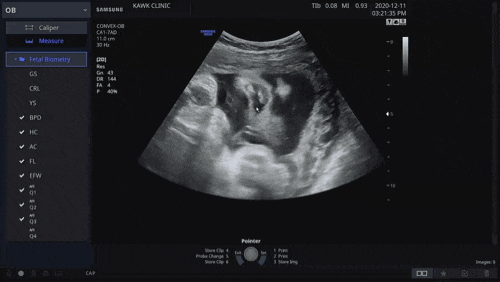

임신 39주차/성남 곽여성병원/내진

임신 39주차 37주때부터 2cm 열려있다해서 일찍 나오나 싶었는데 어느새 40주차를 향해가고있다 ㅋㅋ 언제 ...

임신 38주차/성남 곽여성병원/내진

임신 28주차 토리가 언제 나오나 기다리는 한 주 초음파 BPD = 9.17cm (37주1일) HC = 32...